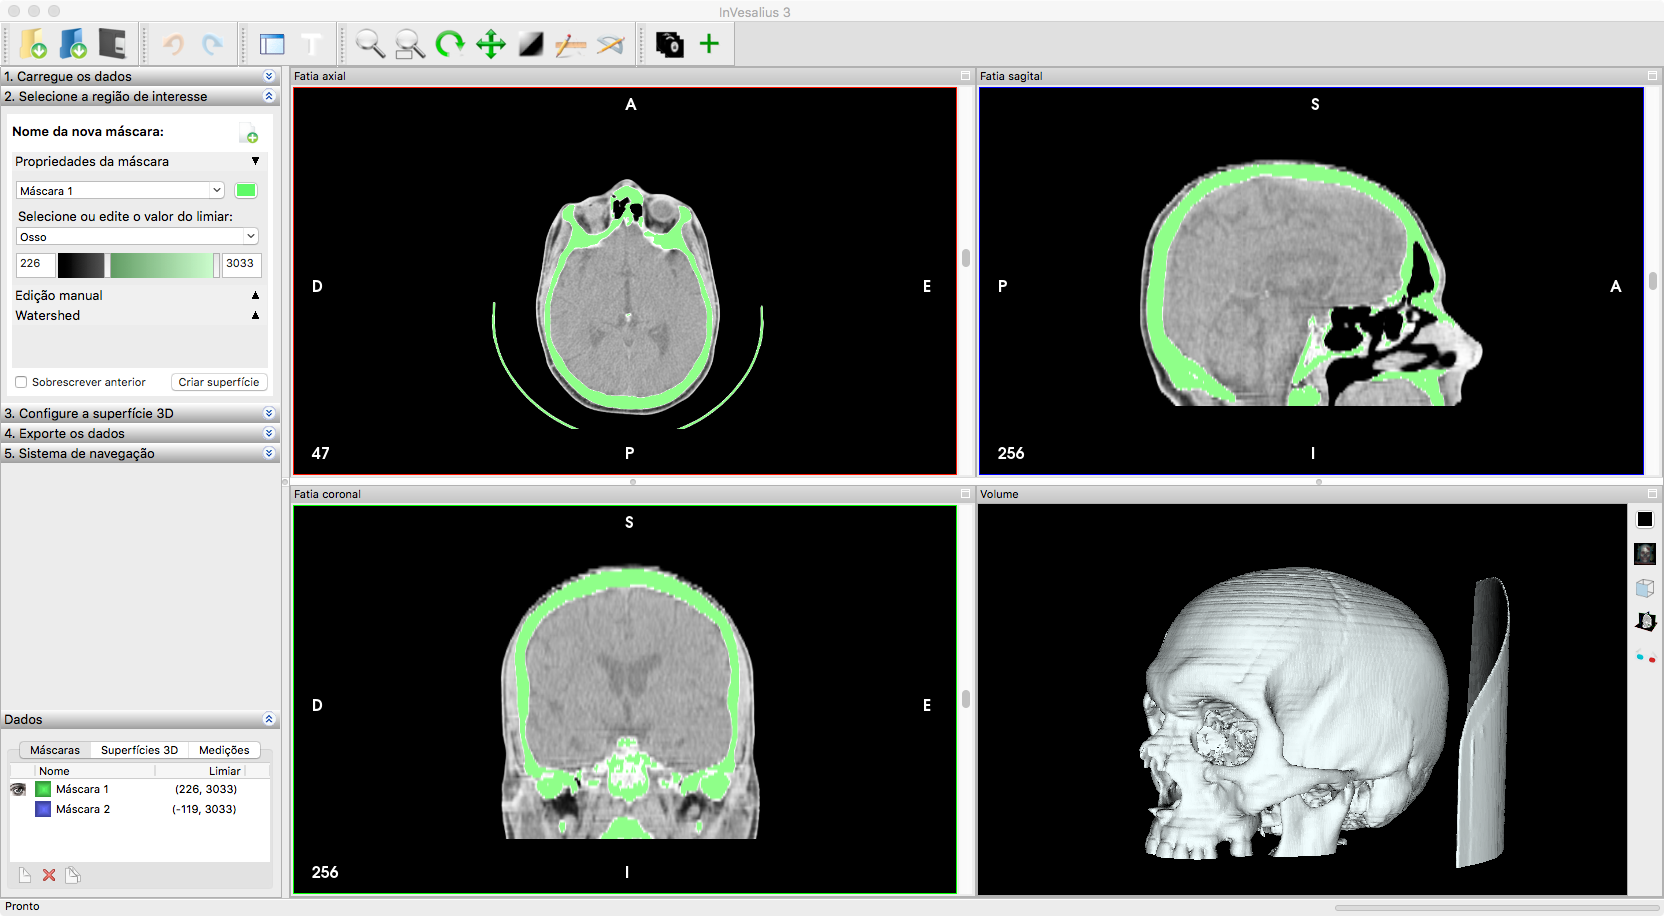

The standard workflow in InVesalius 3 is creating/manipulating masks and transforming them into surfaces. Different tools to edit these masks already exist, whether it is manually or by automatically thresholding certain intensity values (see Figure 2).